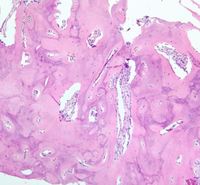

Metabolic bone disease

Category: Red Cell: Other Disorders > Bone/metabolic disease > Anemia of renal osteodystrophy

61 yr old lady, a known case of chronic kidney disease, presenting with pancytopenia